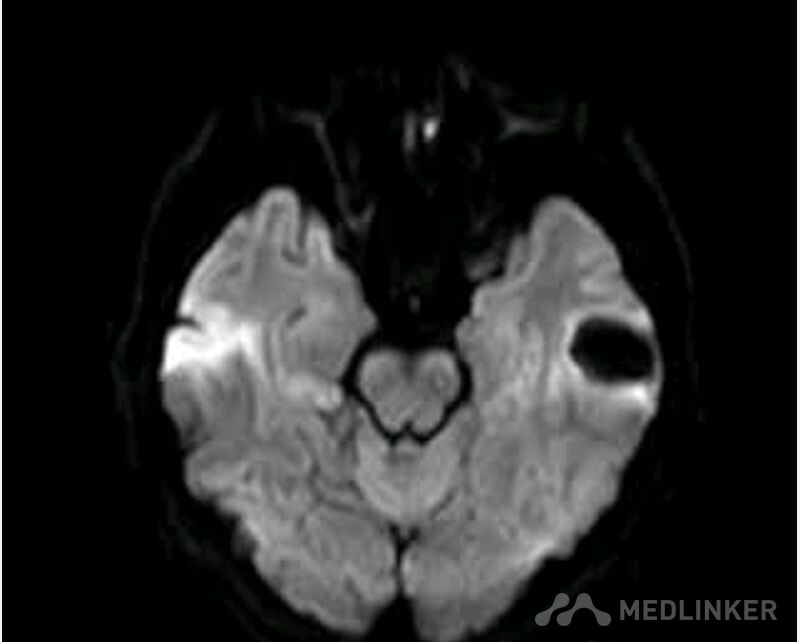

脑囊虫病高清影像资料分享

脑囊虫病经典资料